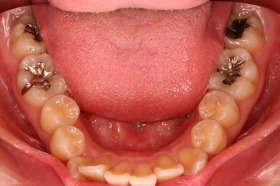

歯の矯正治療 症例ビフォー&アフター

ご覧の症例は出っ歯を矯正治療でキレイにしたケースです。

ご覧の矯正歯科治療の場合は、抜いて矯正歯科

治療していますが東京世田谷矯正歯科センターでは

非抜歯矯正歯科治療をベースにしています。

どうしても抜かないとキレイにならない場合のみ

抜歯して矯正歯科治療しています。